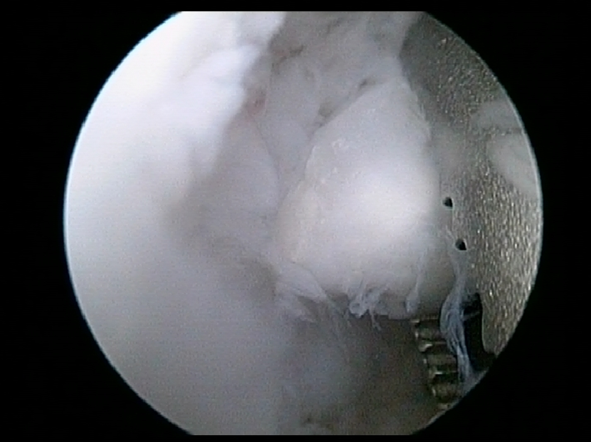

Microfracture Surgery - Wikipedia, The Free Encyclopedia

Through use of an awl, the surgeon creates tiny fractures in the subchondral bone plate. [11] Blood and bone marrow (which contains stem cells) Orthopedic surgery, operations/surgeries and other procedures on bones and joints (ICD-9-CM V3 76–81, ICD-10-PCS 0P–S) Bones: Facial: ... Read Article